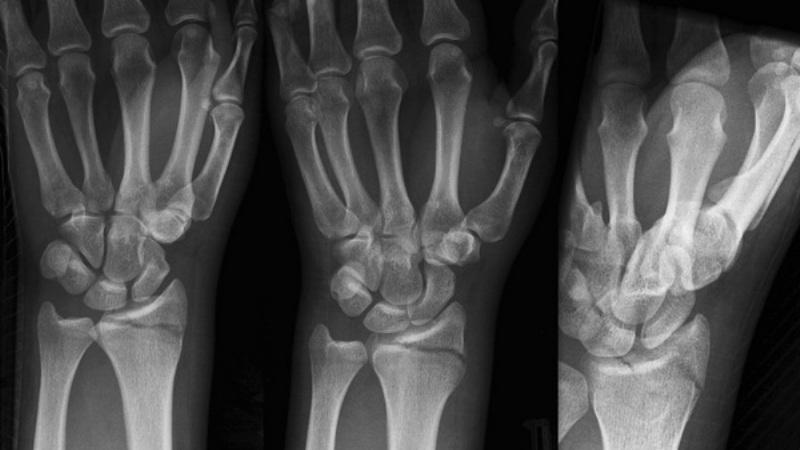

Диагностика перелома

На начальном этапе врач проводит сбор анамнеза заболевания, во время общения с пациентом уточняет детали происшествия и время падения. Затем осуществляется осмотр, после которого пострадавший направляется на рентгенографию лучезапястного сустава в двух проекциях: прямой и боковой.

Если требуется более подробная информация о состоянии мягких тканей, может быть назначена компьютерная томография или ультразвуковое исследование.

Кроме этих случаев, выделяется перелом лучевой кости в типичном месте, так как в результате такой травмы шиловидный отросток также может быть оторван. Различают перелом шиловидного отростка лучевой кости как без смещения, так и со смещением.

Перелом со смещением лучевой кости делится на два типа:

- разгибательный (перелом Коллеса);

- изгибающий (перелом Смита).

Также существует перелом шиловидного отростка локтевой кости, при котором на рентгеновском снимке можно увидеть деформацию контуров конца локтевой кости.